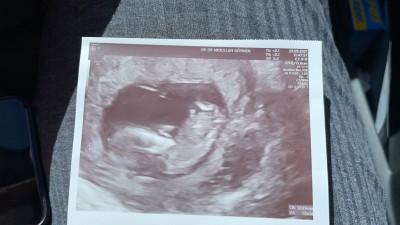

cinsiyet tahmini yaparmisiniz sizce ne 12+ 4 haftalığız

Gebelik haftası 12+4

Doktorda erkeğe benziyor dedi ama kesin değil dedi %30 kızda olabilir dedi